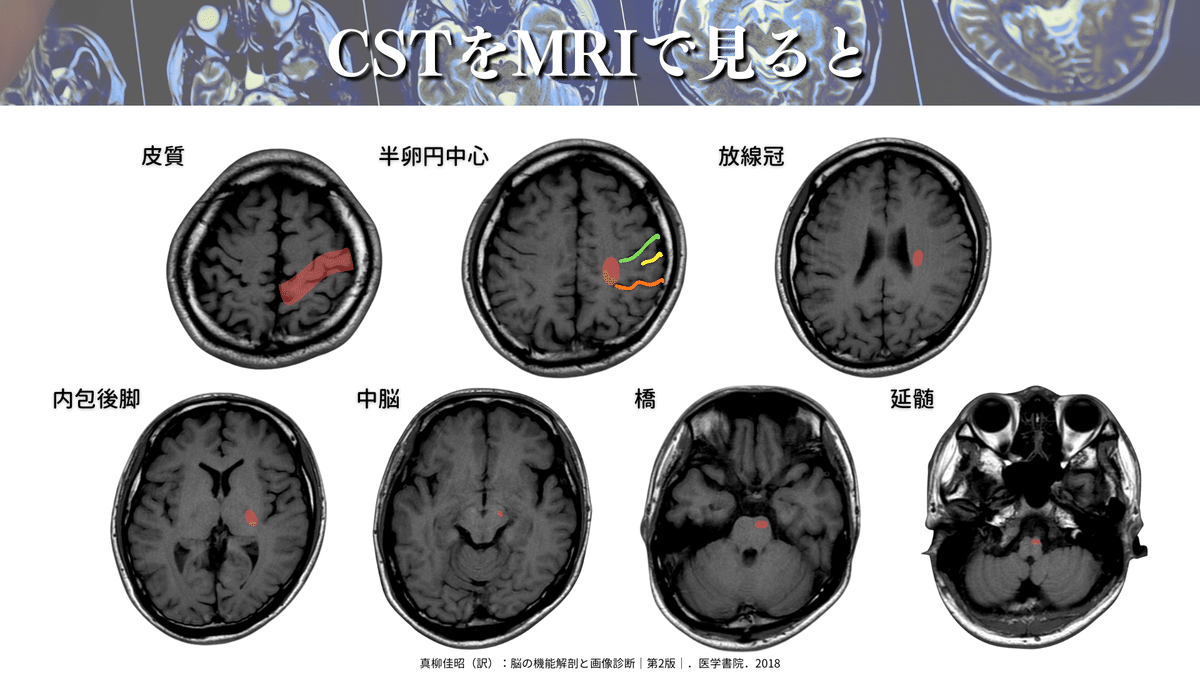

さらに詳しく見ていくと、下図のようなポイントを通過していきます🏃♀️

CSTの代表的な通過ポイント

・一次運動野(6野や3.1.2野からの出力もあります)

・半卵円中心

・放線冠

・内包後脚

・大脳脚(中脳)

・橋

・延髄(錐体交叉)

MRIで見るとこんな感じです⬇️

かなりイメージできてきたのではないでしょうか🤭?

では、それぞれのさらに詳細な読影について解説していきますね✨